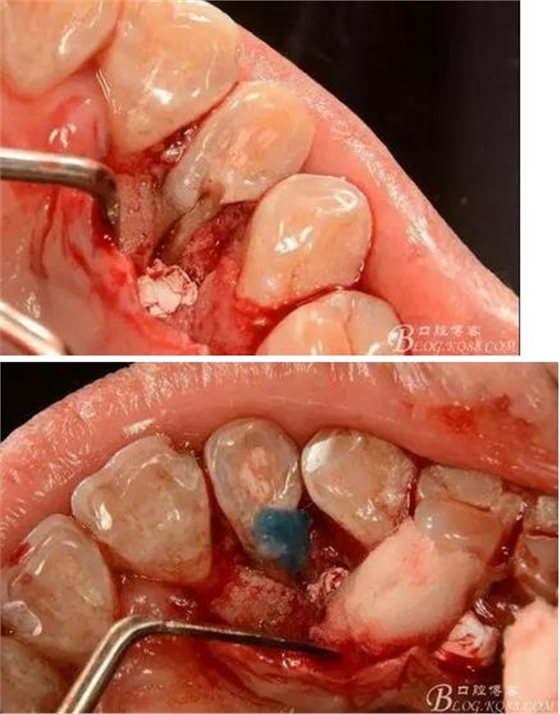

(3)處理:常規(guī)開髓,修整髓腔,15#k銼探查根管,根管測量儀確定工作長度,根長22mm,大錐度手動銼完成根管預(yù)備,沒換一次銼沖洗根管一次,消毒,干燥根管,暫封維他派克斯。4%阿替卡因腎上腺素行11至14局部浸潤麻醉、消毒、鋪巾,做11-14腭側(cè)牙齦水平切口并翻瓣暴露12腭側(cè)骨缺損區(qū),清理肉芽組織及壞死骨組織,清潔術(shù)區(qū),磨除根面溝,制備固位溝槽,酸蝕,粘接,光固化樹脂修復(fù)根面缺損區(qū),阻斷牙周感染途徑。拋光樹脂,沖洗創(chuàng)面,復(fù)位齦瓣,局部敷料壓迫一分鐘,對位縫合齦瓣。術(shù)后抗炎治療,7d線。